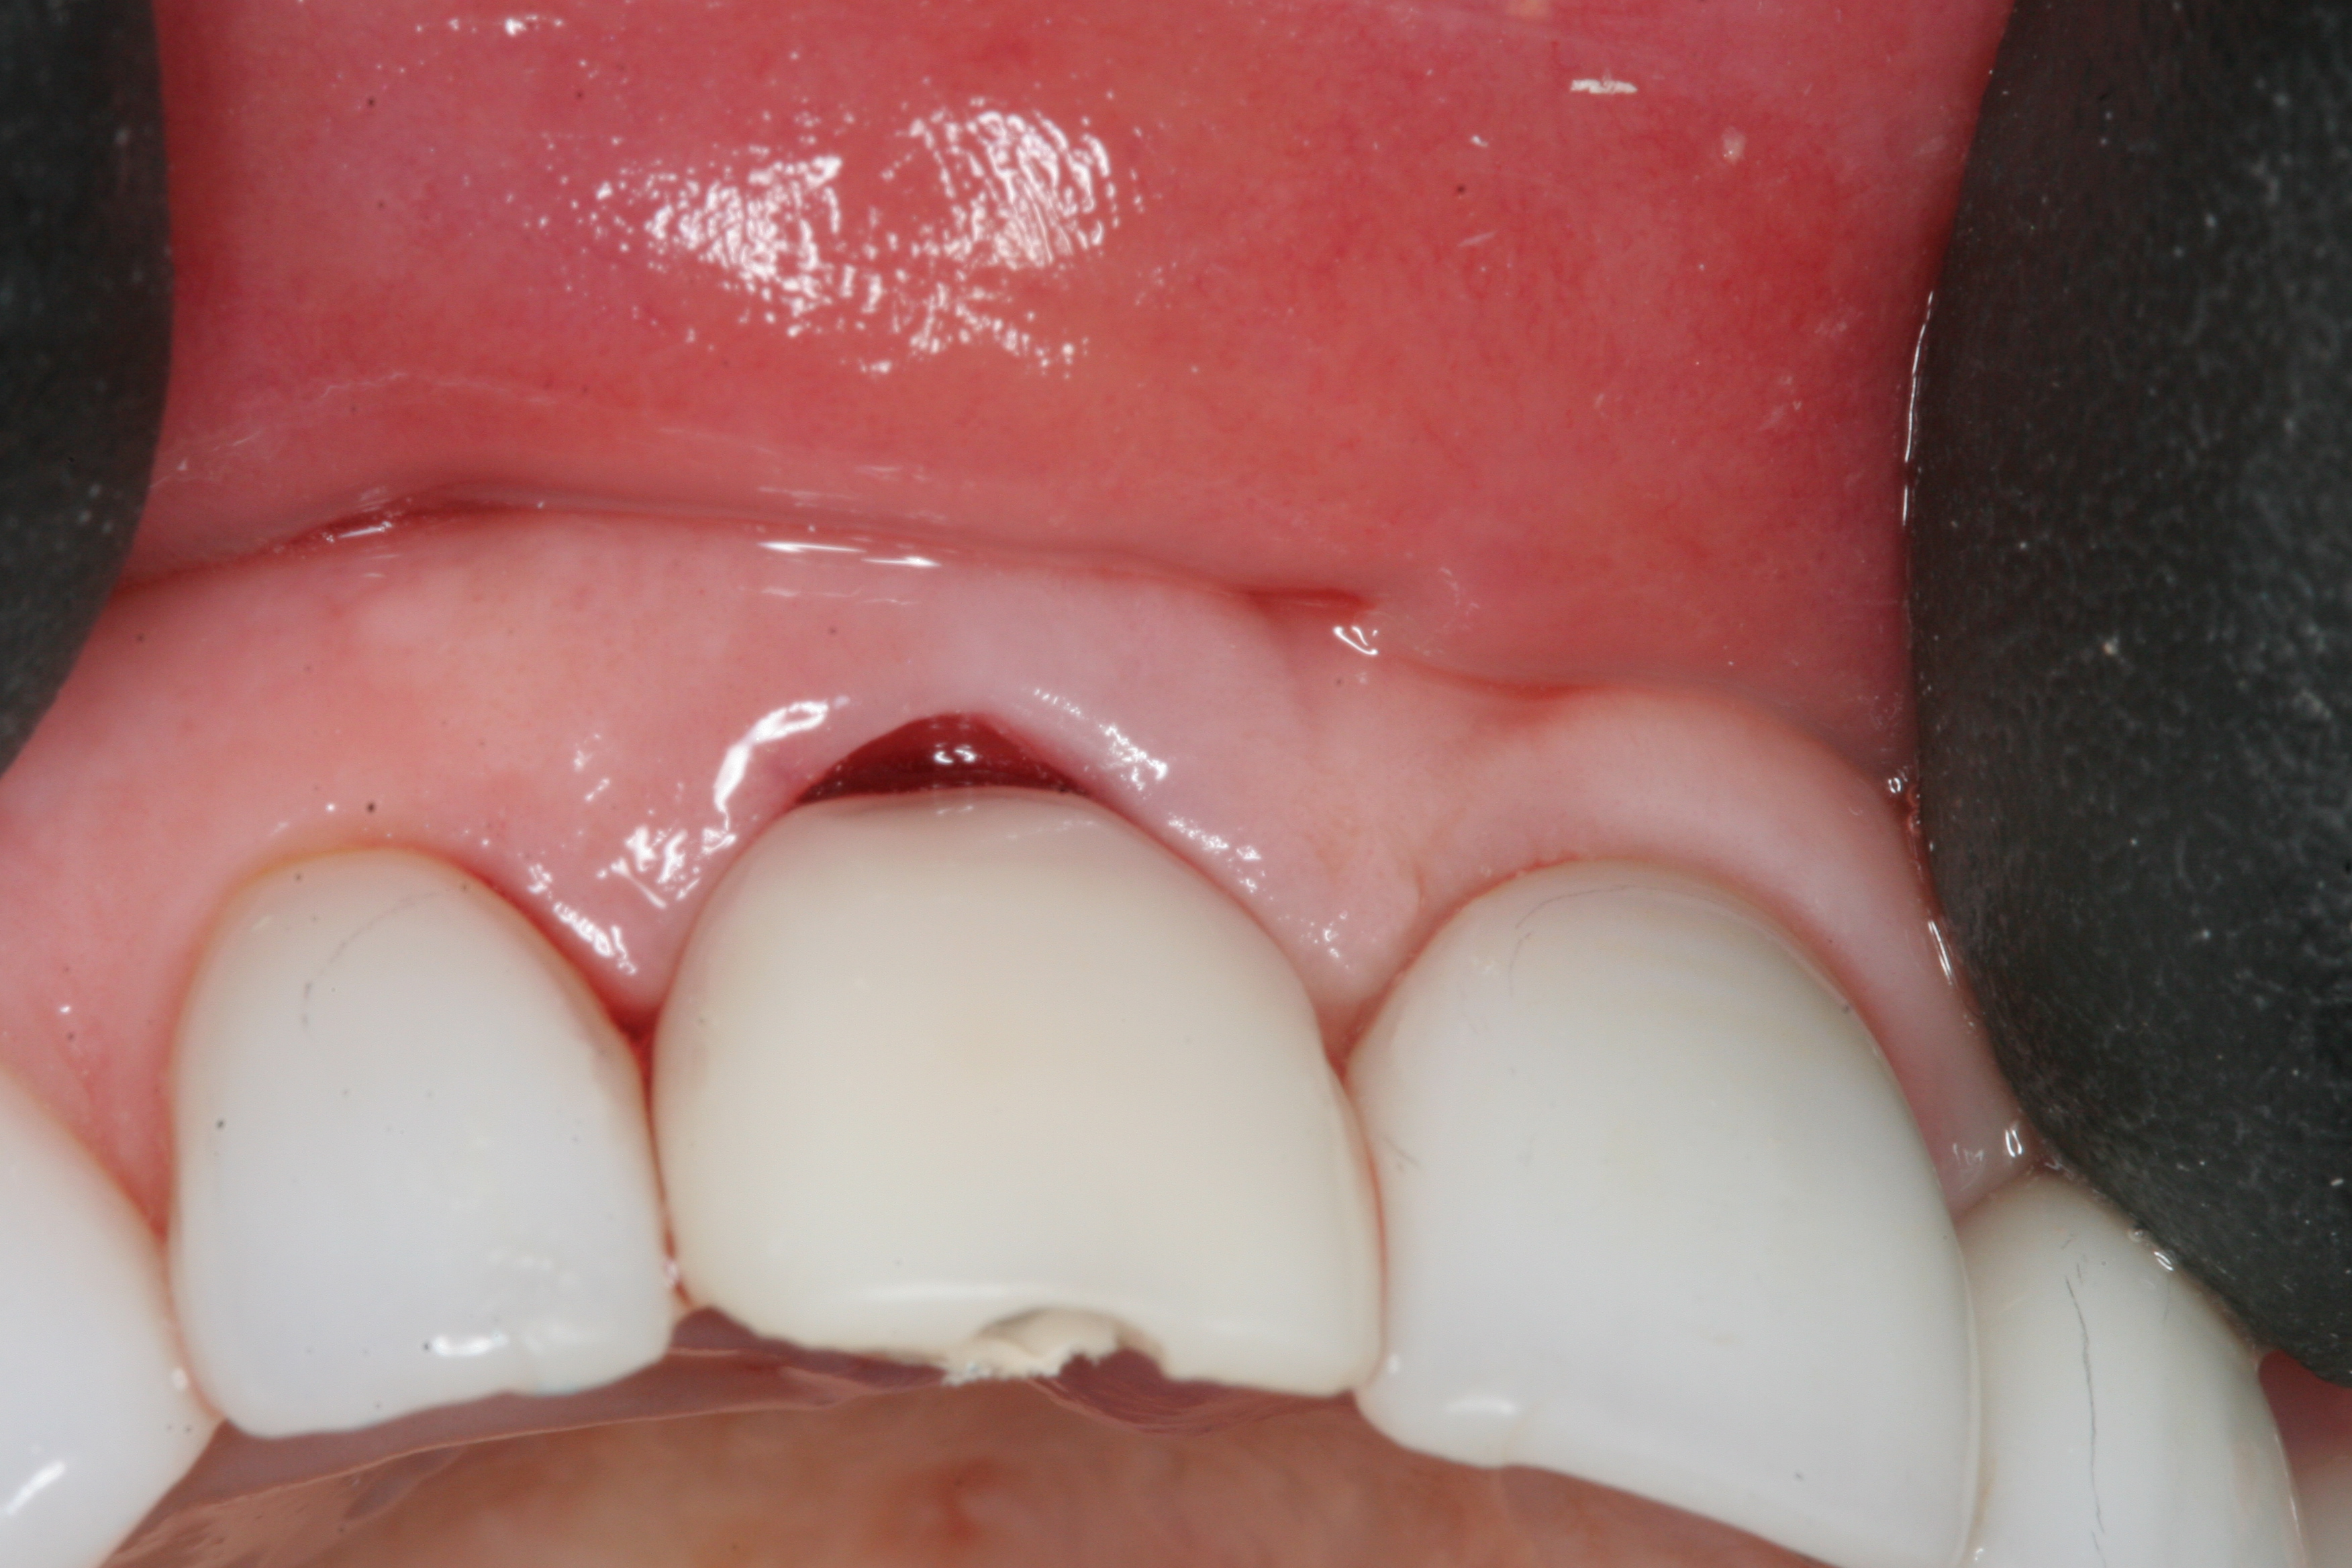

Fig 3. The root tip, after removal of the crown.

Figure 3

Fig 4. The root was atraumatically extracted using periotomes.

Figure 4

Without reflecting a full-thickness mucoperiosteal flap, the root tip was carefully extracted using periotomes to preserve the buccal plate and interproximal bone (Figure 3 and Figure 4). The extraction site was carefully debrided, and an osteotomy was prepared following the manufacturer’s instructions for placement of a 5/4mm D x 13mm L OSSEOTITE® Tapered Certain® PREVAIL® Implant (BIOMET 3i, www.biomet3i.com).